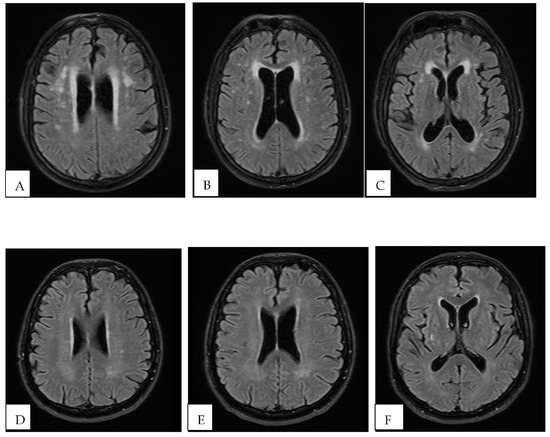

- Chougar, L.; Pyatigorskaya, N.; Degos, B.; Grabli, D.; Lehéricy, S. The Role of Magnetic Resonance Imaging for the Diagnosis of Atypical Parkinsonism. Front. Neurol. 2020, 11, 665. [Google Scholar] [CrossRef]

- Kim, T.W.; Kim, Y.-H.; Kim, K.H.; Chang, W.H. White Matter Hyperintensities and Cognitive Dysfunction in Patients with Infratentorial Stroke. Ann. Rehabil. Med. 2014, 38, 620–627. [Google Scholar] [CrossRef]